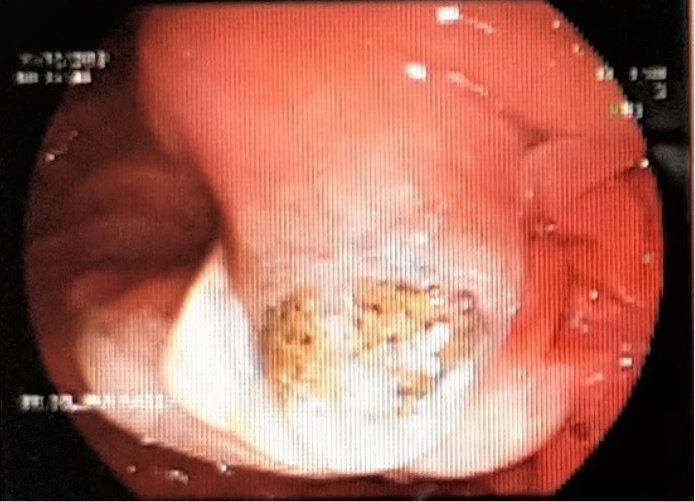

A 59-year-old female with multiple co-morbidities including ischemic heart disease with coronary artery bypass grafting in 2016, diabetes mellitus, hypertension. She presented with fever, abdominal pain related to chronic calcular cholecystitis and poor oral intake referred to examined by general surgery and they recommend to start antibiotics course and to be re-assessed again in a week time. After four days, patient came to the emergency department with severe septic shock, blood pressure as low as 80/40 mmHg refractory to fluids resuscitation. Radiological investigations revealed severe ascending cholangitis, impacted biliary stone at level of ampulla of vater, complicated by liver abscess and anuric acute kidney injury with refractory hyperkalemia and metabolic acidosis requiring urgent renal replacement therapy. Patient was transferred immediately to intensive care unit. In view of dilated biliary radicles with signs of biliary stone impaction, urgent endoscopic retrograde cholangiopancreatography (ERCP) was performed, with stent insertion and pulling out of a large pigmented stone and drainage of biliary muddy fluid (Figure 1). Immediate continuous renal replacement therapy in the form of continuous venovenous hemodiafiltration (CVVHDF) was initiated to correct the metabolic and electrolytes disturbances in order to save the patient life.

A) Pigmented biliary stone obstructing Ampula of Vater.

B) Stent of the common bile duct for drainage.

Figure 1 ERCP and dislodge of impacted biliary stone at ampulla of Vater.